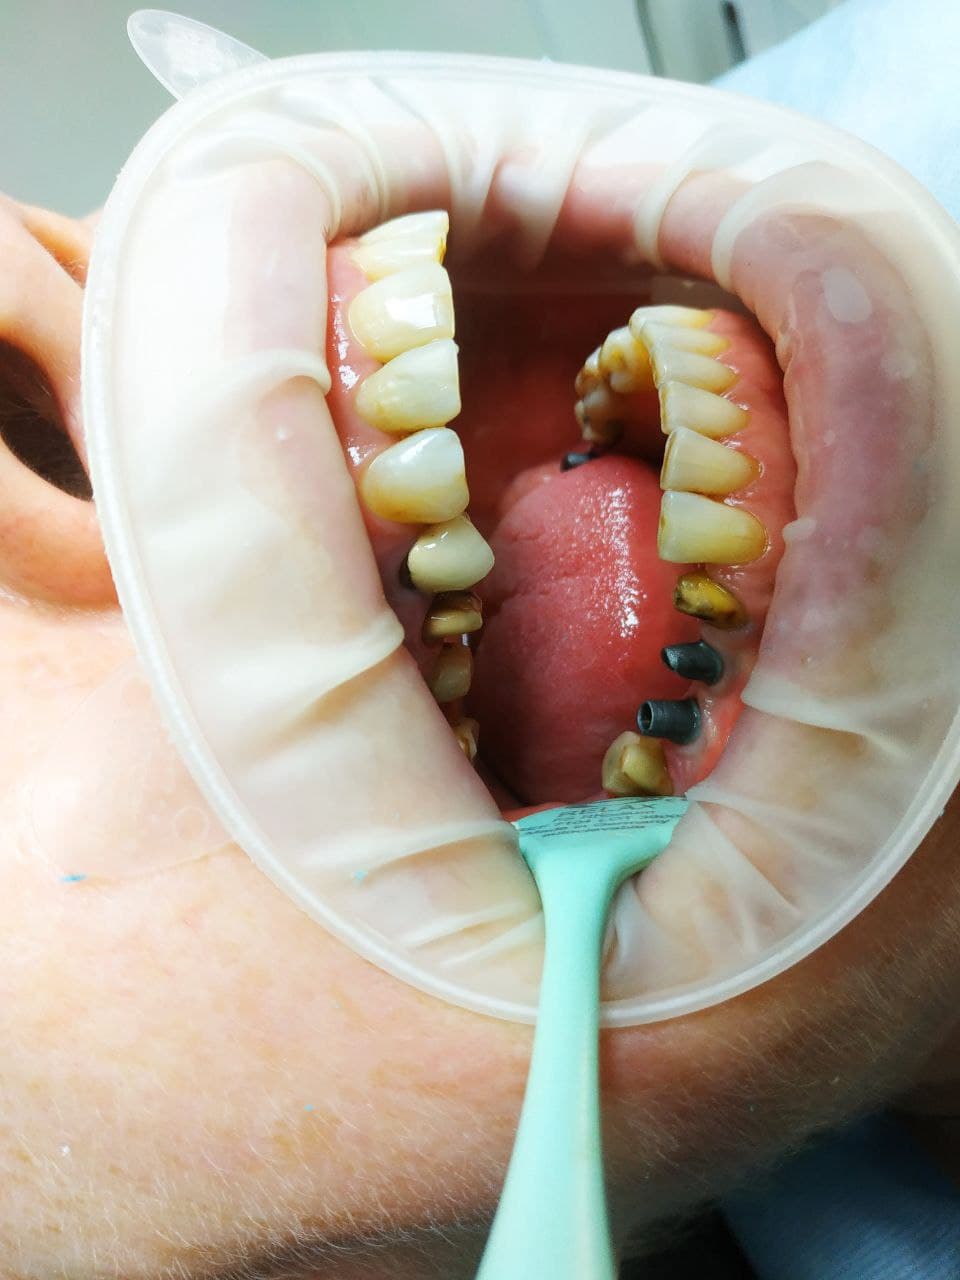

Описание случая: Имплантация при недостаточном объеме кости. Изначальный объем кости был в пределах 3 мм из-за травматичного удаления зубов (выломана картикальная пластинка кости). Для адекватной имплантации минимальный объем - от 6 мм.

Лечение: Принято решение о пересадки ее собственной кости из угла челюсти. Отслоение слизисто-надкостничного лоскута. Забор блока кости в области угла челюсти. Остеопластика блоками + ксенографт. Установка двух имплантов. Наложение швов.

Результаты лечения: Наращивание объема кости до 10 мм. Фиксация имплантов при недостатки костной массы.